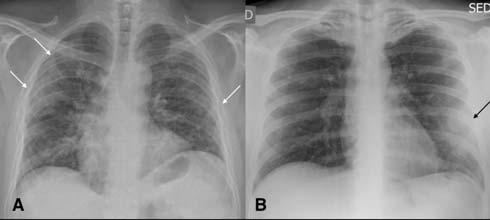

Fig 2 — CXR (A) and CT (B& C) images of a 50-year-old man with 6 days history of fever and dry cough. RT-PCR test was positive. CXR shows bilateral diffuse opacities, with a more opaque patch in the right lower zone (white arrow). The corresponding CT shows the true extent of the disease (black arrows). Images reproduced with permission from Covid-19 Database of the Fleischner Society.

4 — CXR of a 71-year-old man with 4 days history of shortness of breath. Classical features of hazy opacities are seen in the lower lobes bilaterally in a peripheral distribution. Image reproduced with permission from Covid-19 Database of the Fleischner Society.

Fig 7 — Atypical presentation of COVID-19 in the form of nodules (arrows) seen on the CXR (A) and the corresponding CT (B). Image reproduced with permission from Covid-19 Database of the Fleischner Society.